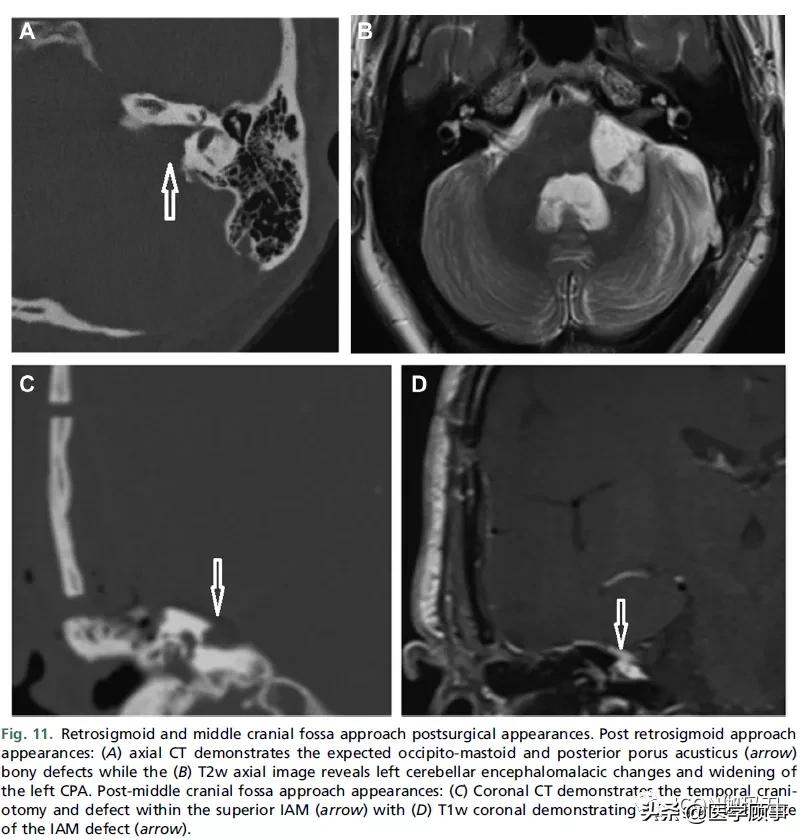

可能需要手术来解决大的或增长的桥小脑角(CPA)的前庭神经鞘瘤(VSs),主要的手术选择是乙状窦后(枕下)或迷路手术入路(图10和11)。中颅窝入路较少用于切除管内肿瘤或有小的耳道外部分的肿瘤。通过迷路和中颅窝的手术路径有保留听力的潜力。表5列出了手术步骤的总结,以及每种手术入路的优点和作用。对于年轻的患者,三叉神经痛的患者,以及有明显囊性成分的患者,手术通常优于放疗。由于放疗引起的肿瘤肿胀会导致面神经或脑干受压缺血,因此手术治疗对较大的肿瘤也有好处。

图11。乙状窦后及中颅窝入路术后表现。乙状窦后入路表现:(A)轴位CT显示预期的枕乳突骨和耳孔后(箭头)骨缺损,(B) T2w轴位CT显示左侧小脑瘤样改变和左侧CPA增宽。颅中窝后入路表现:(C)冠状位CT显示颞部颅骨切开术和内听道缺损(箭头),(D) T1w冠状位CT显示内听道缺损部位的脂肪移植(箭头)。